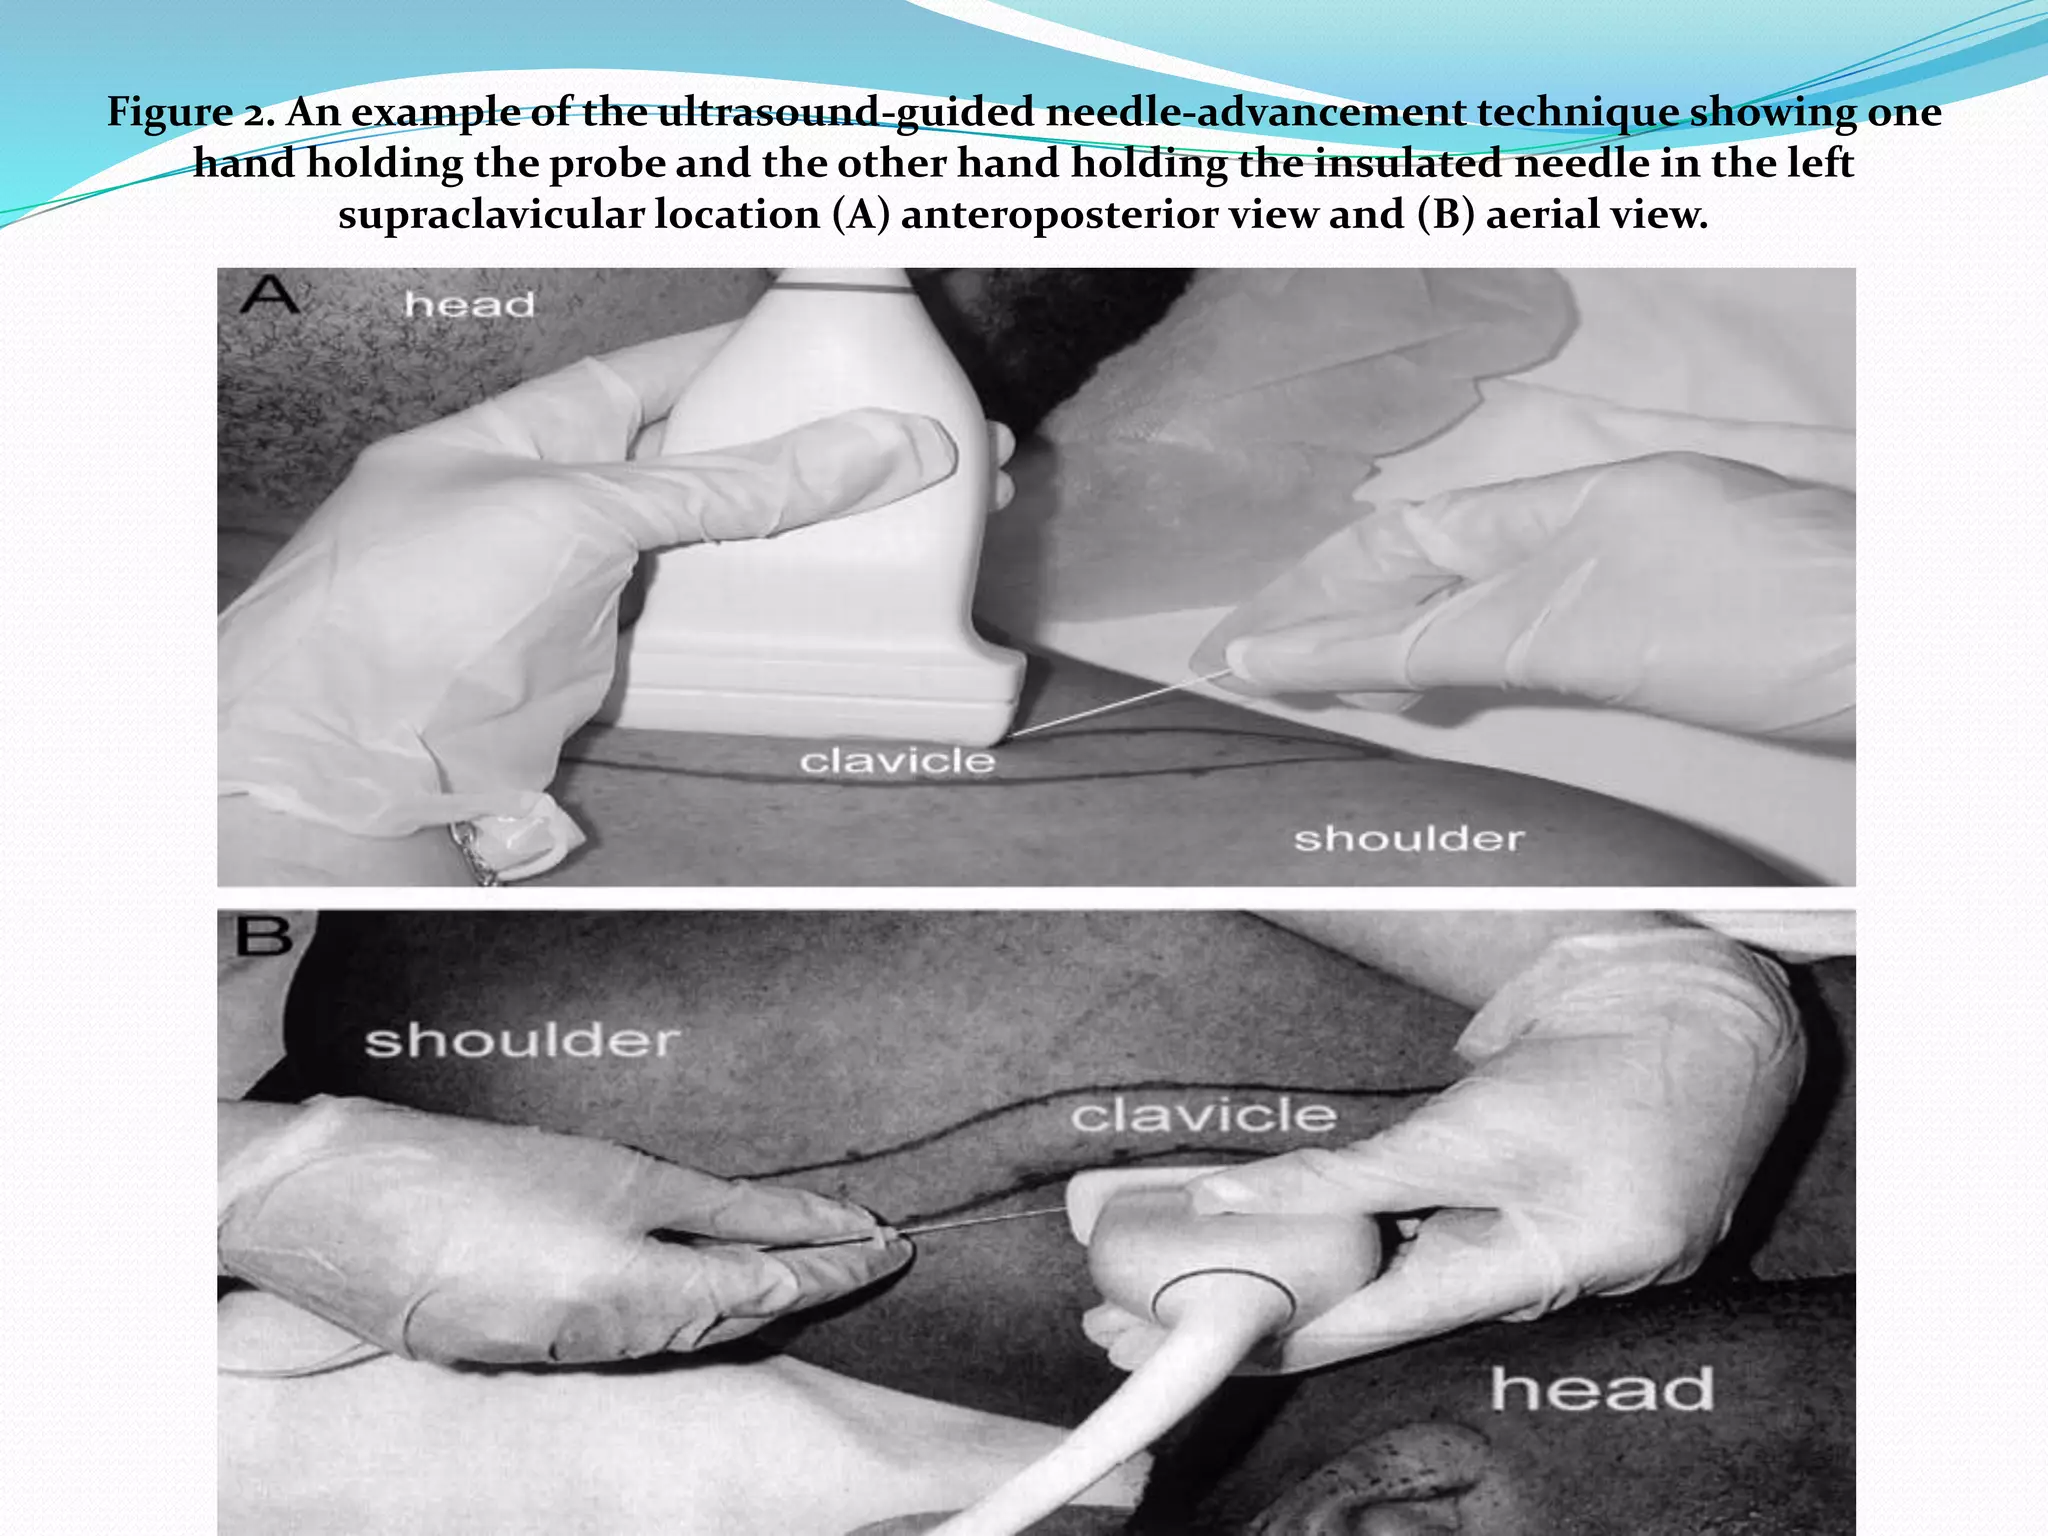

This document provides an overview of brachial plexus anatomy and techniques for brachial plexus nerve blocks. It begins with a description of the brachial plexus formation from cervical and thoracic nerve roots and its branching pattern. Four main approaches for brachial plexus nerve blocks are described: interscalene, supraclavicular, infraclavicular, and axillary. Details are provided on the anatomy and techniques for performing interscalene and supraclavicular brachial plexus blocks. Ultrasound guidance is discussed as an advancement which allows real-time visualization of needle and nerve. Complications are also summarized.